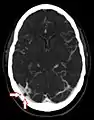

The largest granulations lie along the superior sagittal sinus, a large venous space running from front to back along the center of the head (on the inside of the skull). They are, however, present along other dural sinuses as well.